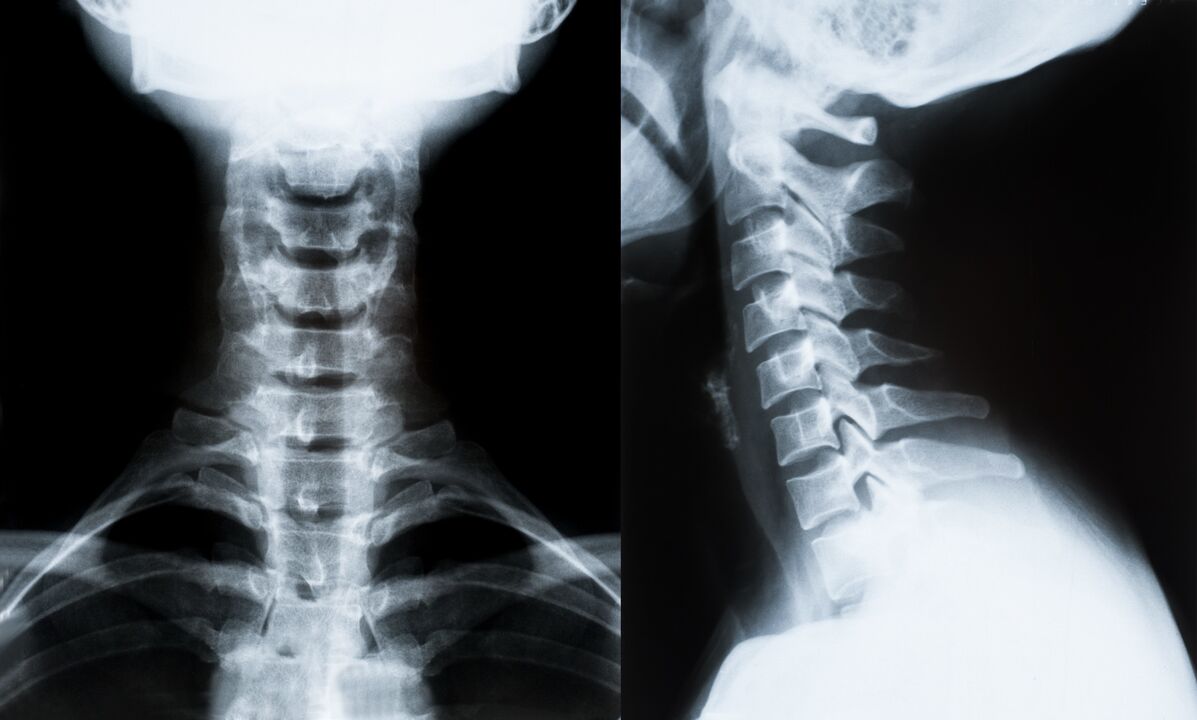

Die wichtigsten Methoden zur Diagnose und weiteren Bestimmung der Behandlung der Osteochondrose der Halswirbelsäule:

- Röntgenstrahlen. Die am wenigsten wirksame, aber traditionelle Diagnosemethode.

- Die Magnetresonanztomographie ist die effektivste Diagnosemethode. Bei dieser Art der Patientenuntersuchung sind alle notwendigen Strukturen sichtbar.

- Ist es notwendig, Veränderungen zu messen, kommt die Computertomographie zum Einsatz. Bestimmt das Vorhandensein von Hernien und anderen Dingen.

- Die letzte Methode ist die Duplex-Ultraschalluntersuchung. Diese Forschungsmethode bestimmt die Geschwindigkeit des Blutflusses in den Arterien.

Es ist unmöglich, eine Wirbelsäulenerkrankung zu Hause genau zu bestimmen.